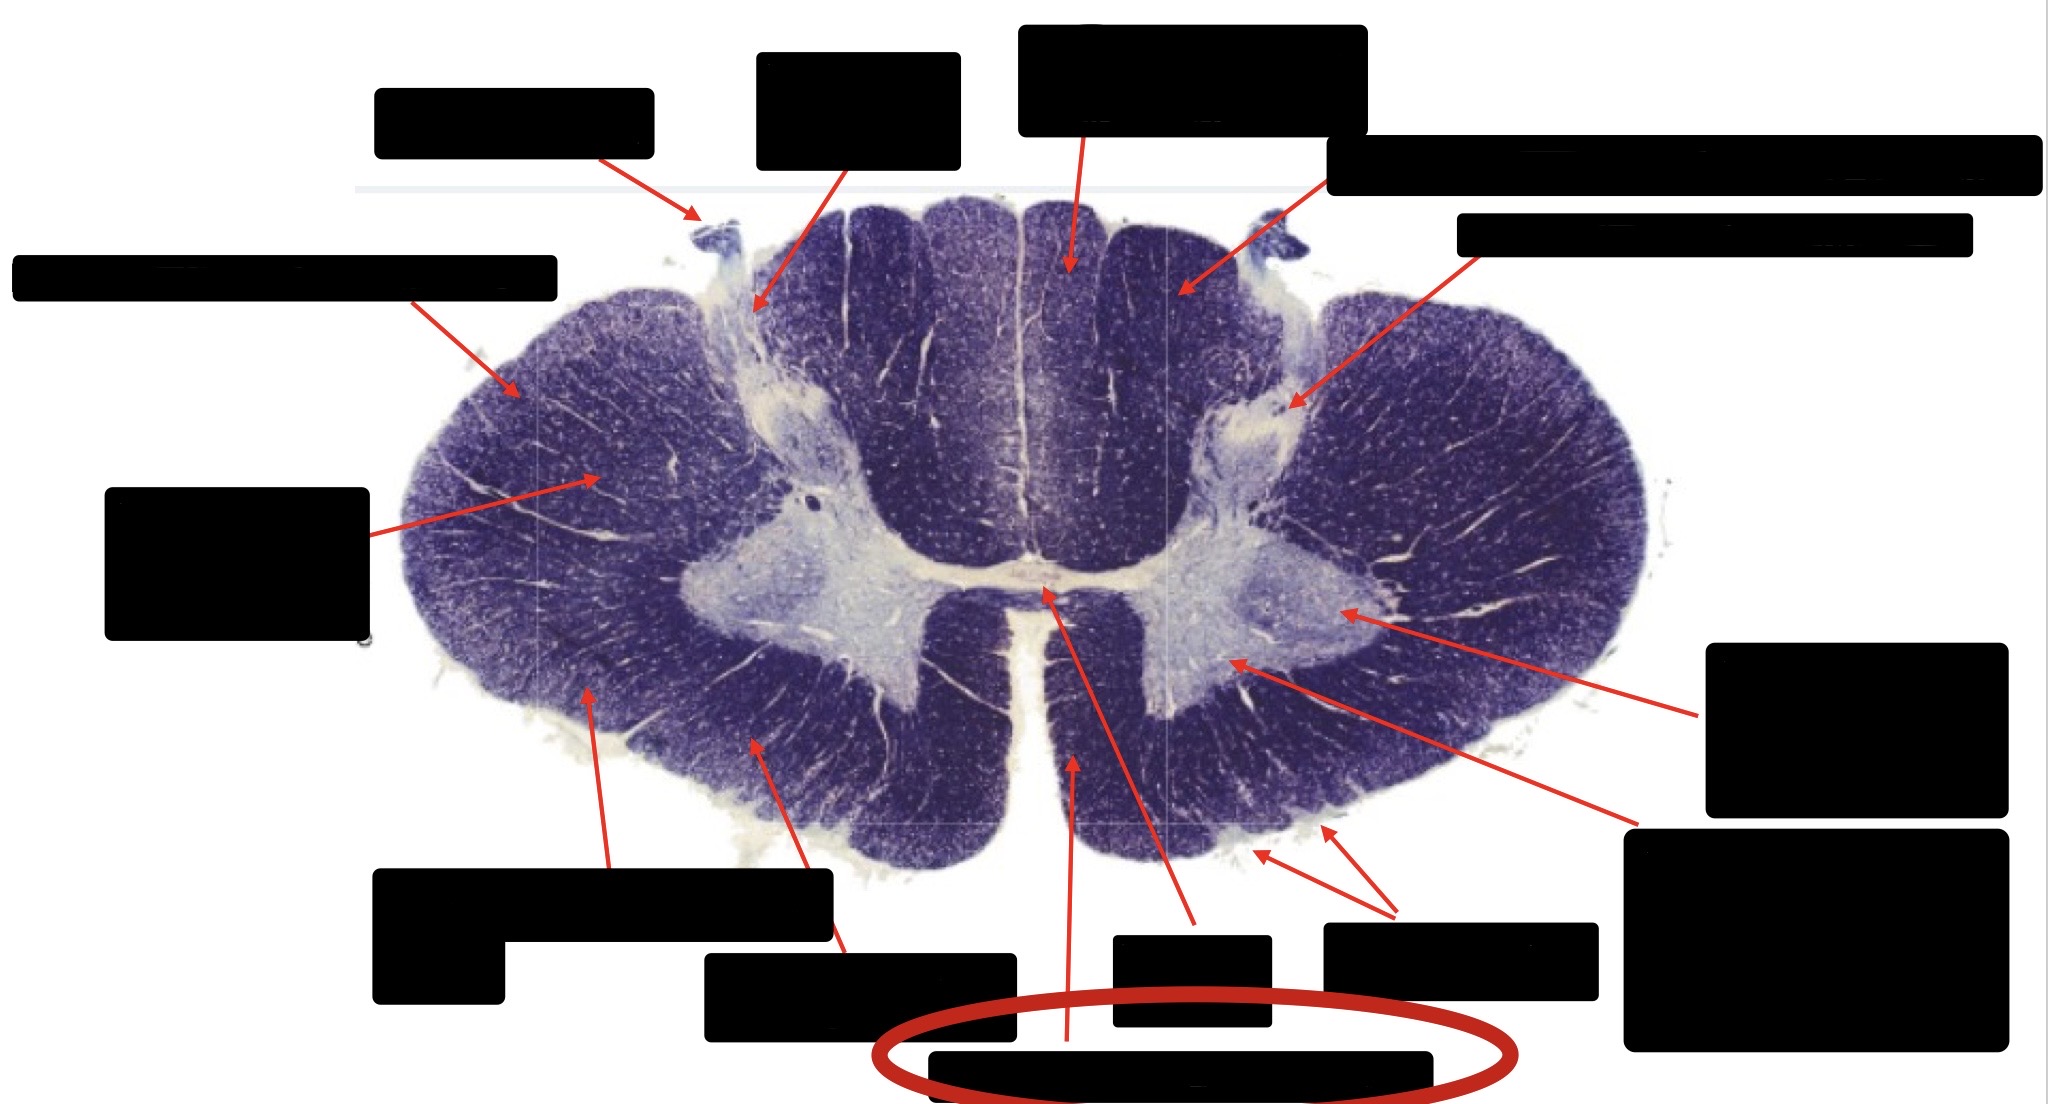

Central Canal

Posterior Column (Fasciculus Gracilis)

Large Fiber Entry Zone

Lissaeur’s Tract & Small Fiber Entry Zone

Substantia Gelatinosa

Lateral Corticospinal Tract

Ventral Root Fibers

Anterior Horn Motor Neurons

Anterior Medial Fissure

Dorsal Rootlet

Posterior Spinocerebellar Tract

Anterior Spinocerebellar Tract

Spinothalmic Tract

Posterior Column (Fasciculus Cuneatus)

Anterior Horn Motor Neurons (Distal Muscles)

Anterior Horn Motor Neurons (Proximal Muscles)